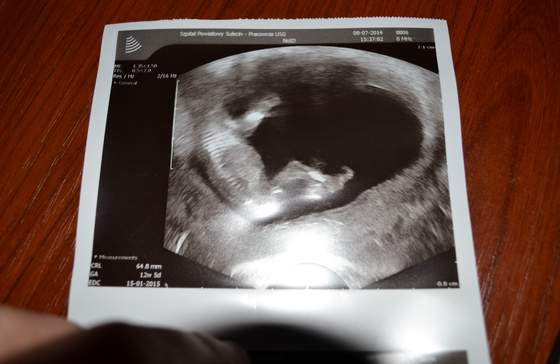

A tu nasz robak

i jego długie nogi, dlatego twierdzę, że to laska z taaakimi nogami

A i dzisiaj na usg wiek dziecka wyszedł idealnie jak wiek według OM, więc oba terminy porodu mi się pokryły. :)